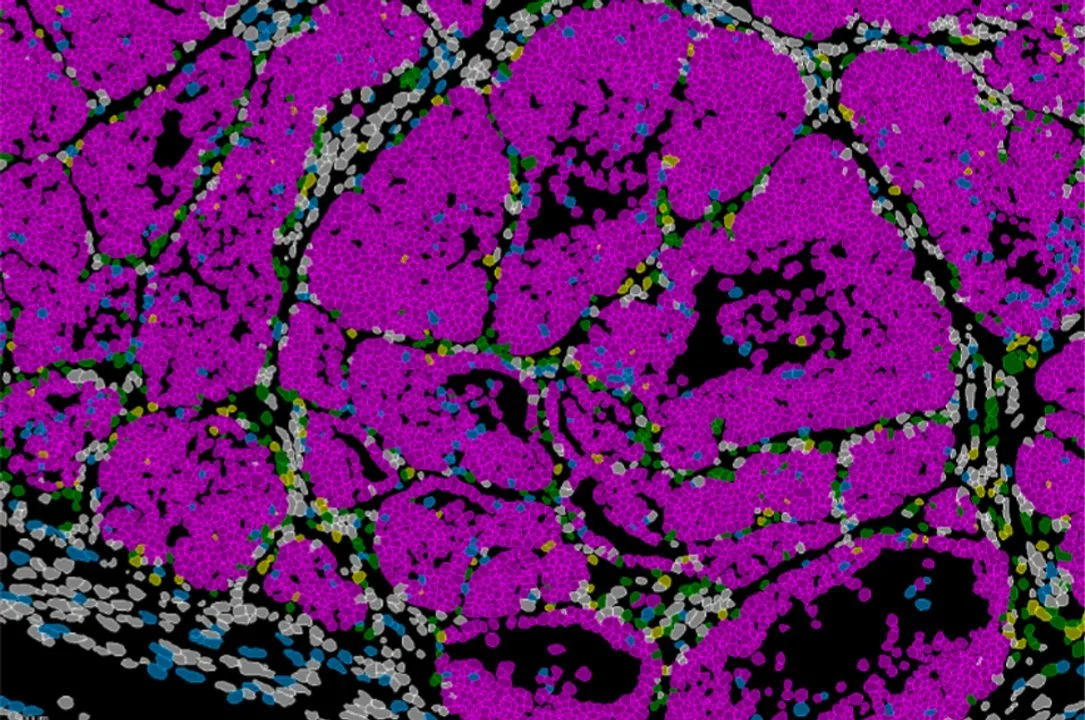

El trabajo muestra una población de células en el borde invasivo del tumor capaz de invadir y dividirse o de entrar en letargo. El gen Prrx1 es el encargado de regular este equilibrio, que determina la formación de nuevos focos tumorales en otros órganos, las temidas metástasis.

Este nuevo estudio, desarrollado por el laboratorio de Plasticidad Celular en Desarrollo y Enfermedad, dirigido por Ángela Nieto, demuestra que la capacidad metastásica no surge por azar ni depende únicamente del microambiente del órgano de destino. Por el contrario, el potencial metastásico ya está determinado en un conjunto de células presentes en el tumor que origina el cáncer. Estas células adoptan un estado altamente metastásico coordinado por un factor clave: el gen Prrx1.

El equipo combinó modelos genéticos en ratón, análisis de célula única, estudios de cromatina y técnicas de transcriptómica espacial que permiten observar la organización y el comportamiento de las células directamente en el tejido tumoral.

De esa manera, los investigadores analizaron muestras de pacientes con cáncer de mama y detectaron patrones similares de expresión de Prrx1, lo que sugiere que el mecanismo descrito podría tener una relevancia directa en la clasificación y el pronóstico clínico.